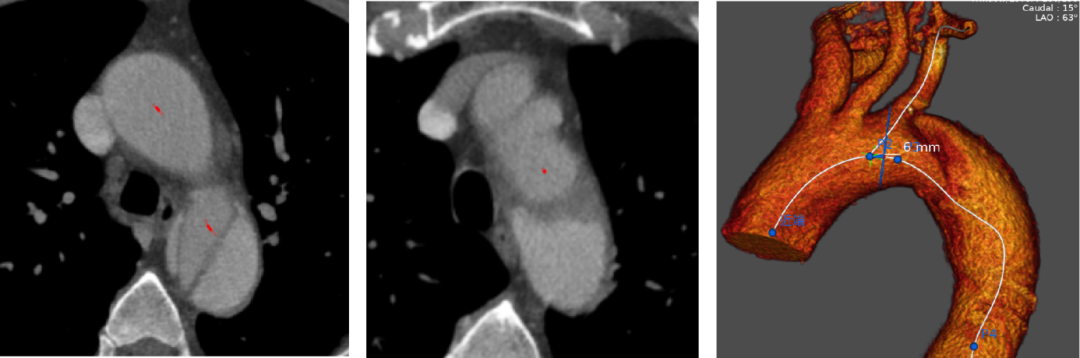

患者为51岁男性,因“胸背痛8小时”入院,主动脉CTA示Stanford B型主动脉夹层,夹层累及主动脉弓部、真腔受压、假腔扩张,手术指征明确。

术前周庆教授团队为其手术方案进行充分评估,拟采用微创介入的方法治疗,但夹层近端破口距左锁骨下动脉开口约2cm,且夹层累及了左锁骨下动脉开口,要封闭破口,必须将锚定区延伸至左颈总动脉开口后缘。综合患者解剖条件及微创要求,周庆教授团队决定为患者行主动脉腔内隔绝术,并以原位开窗技术重建左锁骨下动脉血供。

术中,在杂交手术室,周庆教授团队首先经股动脉入路植入先健36*200mm胸主动脉支架,支架近端置于左颈总动脉开口后缘,然后经左肱动脉送入球囊穿刺针成功破膜,再送入球囊扩张穿刺点,以一枚12*40mm血管覆膜支架重建左锁骨下动脉血供。术后造影提示支架形态良好,主动脉夹层近端破口完全封闭,无造影剂渗漏,左颈总动脉及左锁骨下动脉血流通畅,完美达到了术前预定目标。

手术方案

影像分析显示,破口位于弓降部小弯侧,近端累及LSA后侧壁,颈锁距离为6mm。